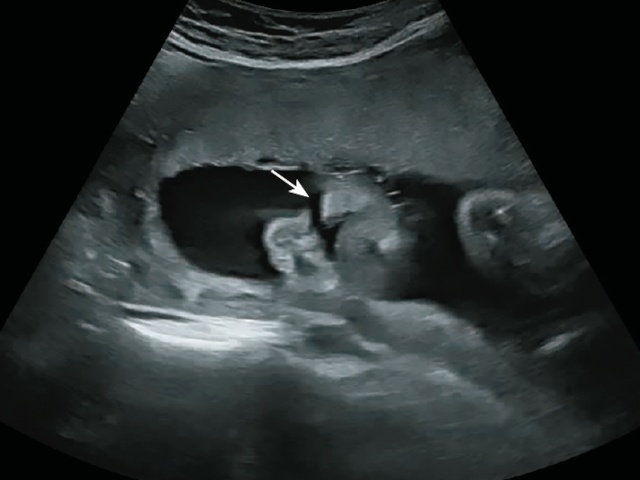

Беременность 17 нед. Пациентка обратилась впервые. В сагиттальном срезе определяется значительный дефект средней линии лица (рис. 22). Отсутствует четкая визуализация кончика носа, имеется премаксиллярная протрузия. Также в сагиттальном срезе отсутствует визуализация нёбного отростка верхней челюсти (рис. 23). При движении языком («посасывании») определяется перемещение языка плода в носовую полость (рис. 24).

Рис. 24. Отсутствие визуализации твердого нёба. Кончик языка плода расположен в полости носа (белая стрелка). Премаксиллярный выступ (желтая стрелка).

В аксиальном срезе выявлен большой дефект в альвеолярной дуге верхней челюсти (рис. 25).

Рис. 25. Большой дефект верхней челюсти (белая стрелка).